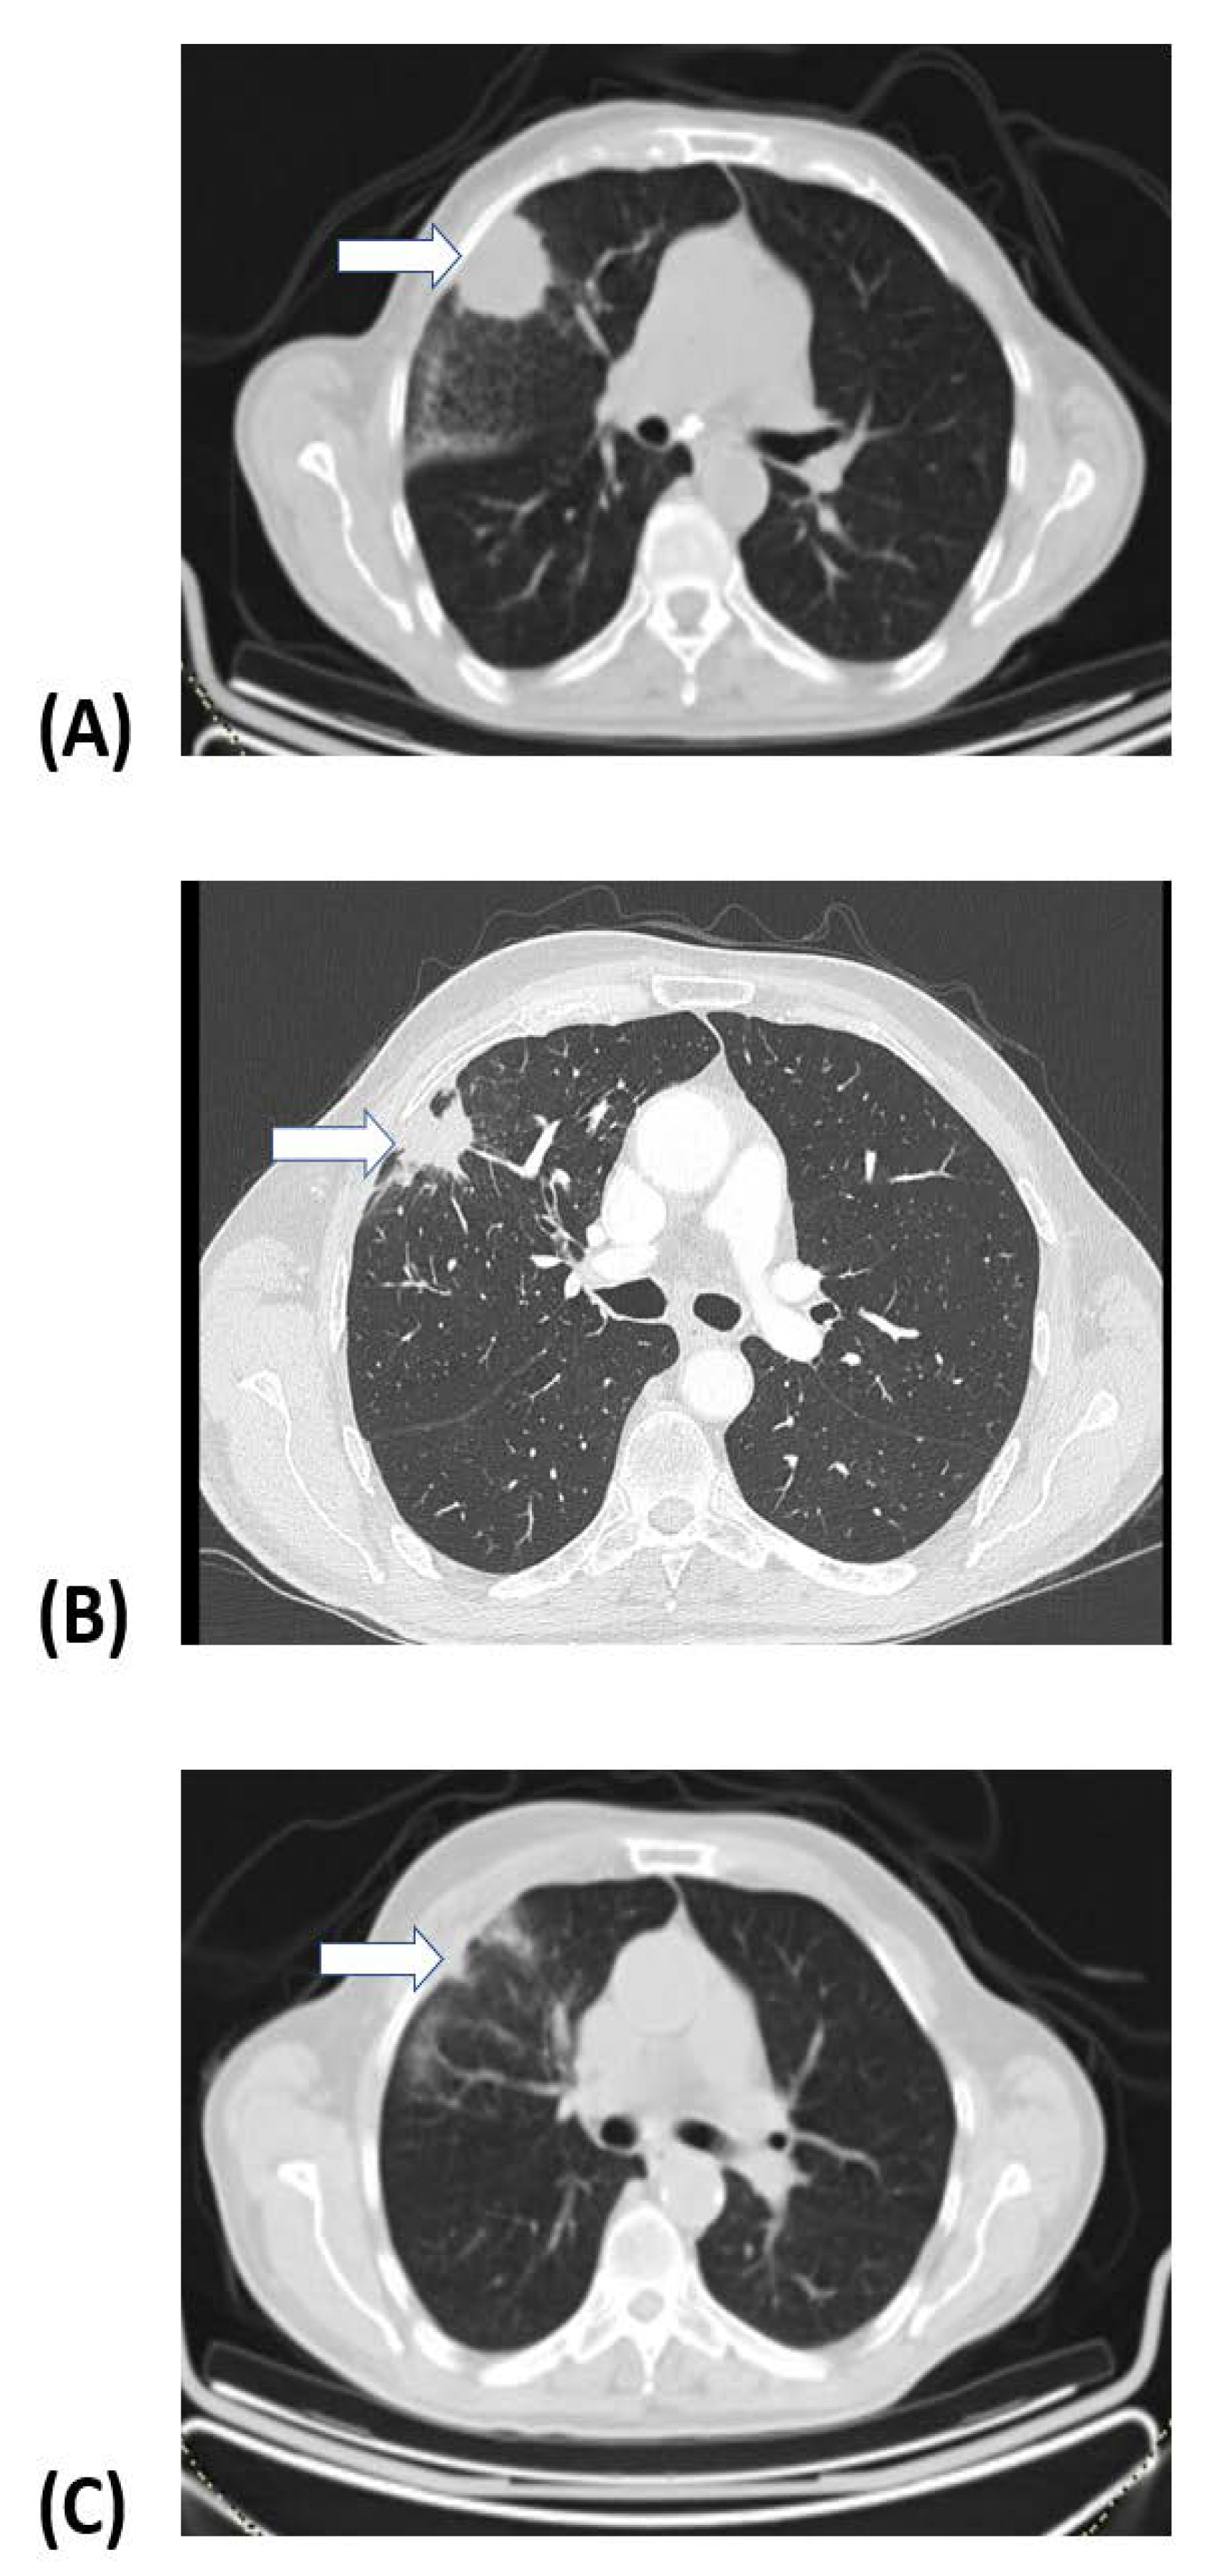

3.1. Treatment Response and Survival